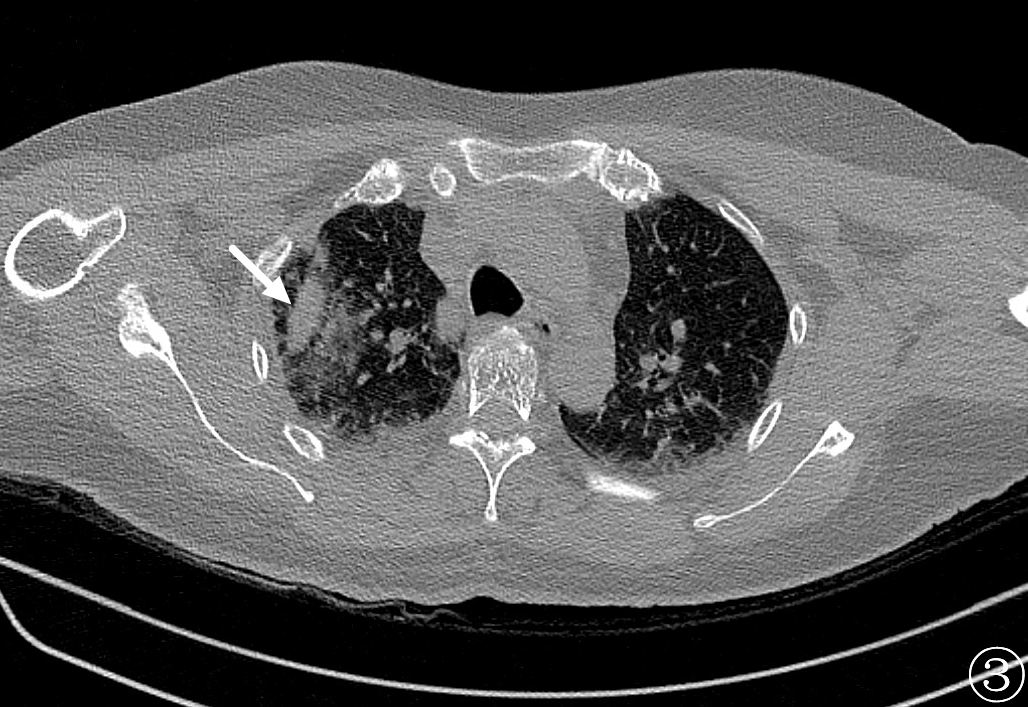

术前进行常规CT扫描确定消融区域及穿刺路径,局部麻醉后利用微波消融针,从体表定位点沿着穿刺路径逐层穿刺到达预定消融区域(图②),予以单次多点消融靶区,最后可见消融后靶区完全覆盖病变区域(图③、④)。手术过程仅耗时约1h,术中肺尖可见少量出血,未发现气胸及咯血等并发症,术后3天复查影像可见消融区完全覆盖病灶(图⑤),病人安然出院,从而达到治愈性消融的目的。